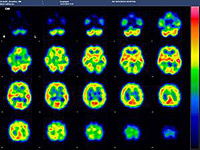

脳血流シンチ